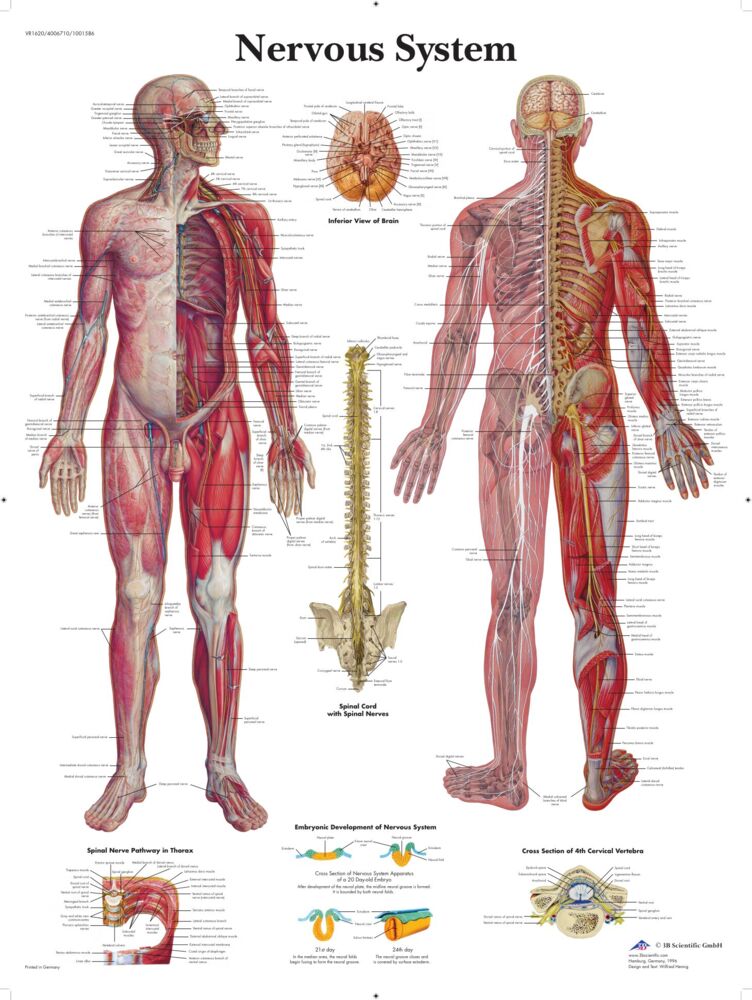

Nervsystemet plansch

Laminerad anatomisk affisch av det mänskliga nervsystemet i färgstarka detaljer. Plans...

Laminerad anatomisk affisch av det mänskliga nervsystemet i färgstarka detaljer. Planschen beskriver hela det mänskliga nervsystemet, inklusive den mänskliga hjärnan och ryggmärgen och är därför ett bra komplement till vårdmottagningar och klassrum. Tryckt på 200 g UV-beständigt papper och laminerad (75 µm) på båda sidor, vilket gör den stadig samt att den inte bleknar i solen. Lamineringen gör dessutom att ytan går att skrivas på med icke-permanenta färgpennor. Engelsk text.